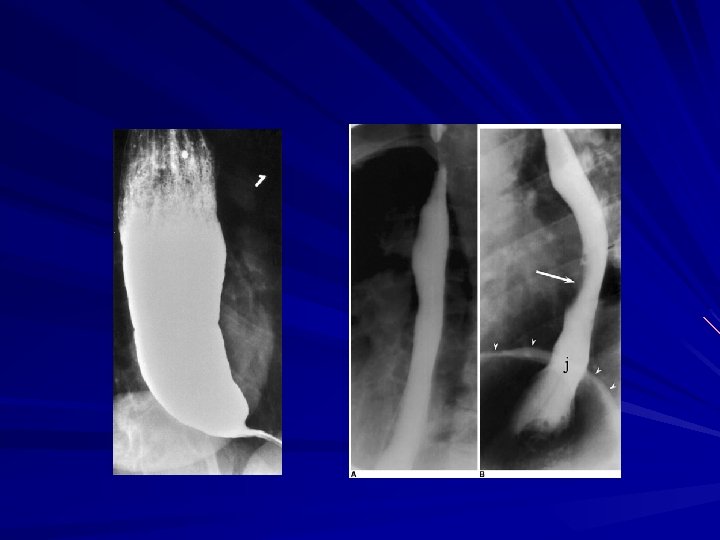

Pharyngoesophageal (Zenker's) Diverticulum is the most common esophageal diverticulum found today It usually presents in older patients in the 7 th decade of life found herniating into Killian's triangle, between the oblique fibers of the thyropharyngeus muscle and the horizontal fibers of the cricopharyngeus muscle

Symptoms and Diagnosis Commonly, patients complain of a sticking in the throat. nagging cough, excessive salivation, and intermittent dysphagia often are signs of progressive disease As the sac increases in size, regurgitation of foul-smelling, undigested material is common

Symptoms and Diagnosis Halitosis, voice changes, retrosternal pain, and respiratory infections are especially common in the elderly population The most serious complication from an untreated Zenker's diverticulum is aspiration pneumonia or lung abscess

Symptoms and Diagnosis is made by barium esophagram Neither esophageal manometry nor endoscopy is needed to make a diagnosis of Zenker's diverticulum.

Diffuse Esophageal Spasm DES is a hypermotility disorder of the esophagus is seen most often in women and is often found in patients with multiple complaints The basic pathology is related to a motor abnormality of the esophageal body that is most notable in the lower two thirds of the esophagus

Diffuse Esophageal Spasm the esophageal contractions are repetitive, simultaneous, and of high amplitude

Symptoms and Diagnosis The clinical presentation of DES is typically that of chest pain and dysphagia These symptoms may be related to eating or exertion and may mimic angina Patients will complain of a squeezing pressure in the chest that may radiate to the jaw, arms, and upper back

Symptoms and Diagnosis The symptoms are often pronounced during times of heightened emotional stress Regurgitation of esophageal contents and saliva is common, but acid reflux is not acid reflux can aggravate the symptoms, as can cold liquids

Symptoms and Diagnosis irritable bowel syndrome and pyloric spasm, may accompany DES, whereas other gastrointestinal problems, such as gallstones, peptic ulcer disease, and pancreatitis, all trigger DES The diagnosis of DES is made by an esophagram and manometric studies